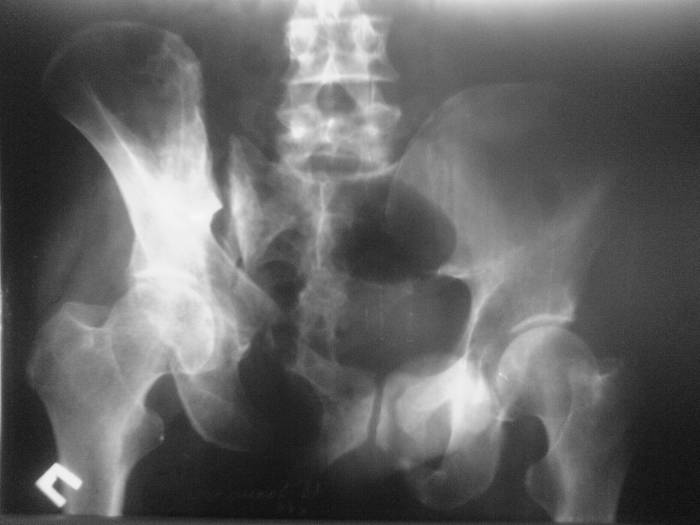

Вложение не в текстовом формате было извлечено…

Имя     : Outlet.jpg

Тип     : image/jpeg

Размер  : 26179 байтов

Описание: отсутствует

Url     : http://weborto.net:8080/pipermail/ortho/attachments/20070616/f45c096c/attachment-0005.jpg